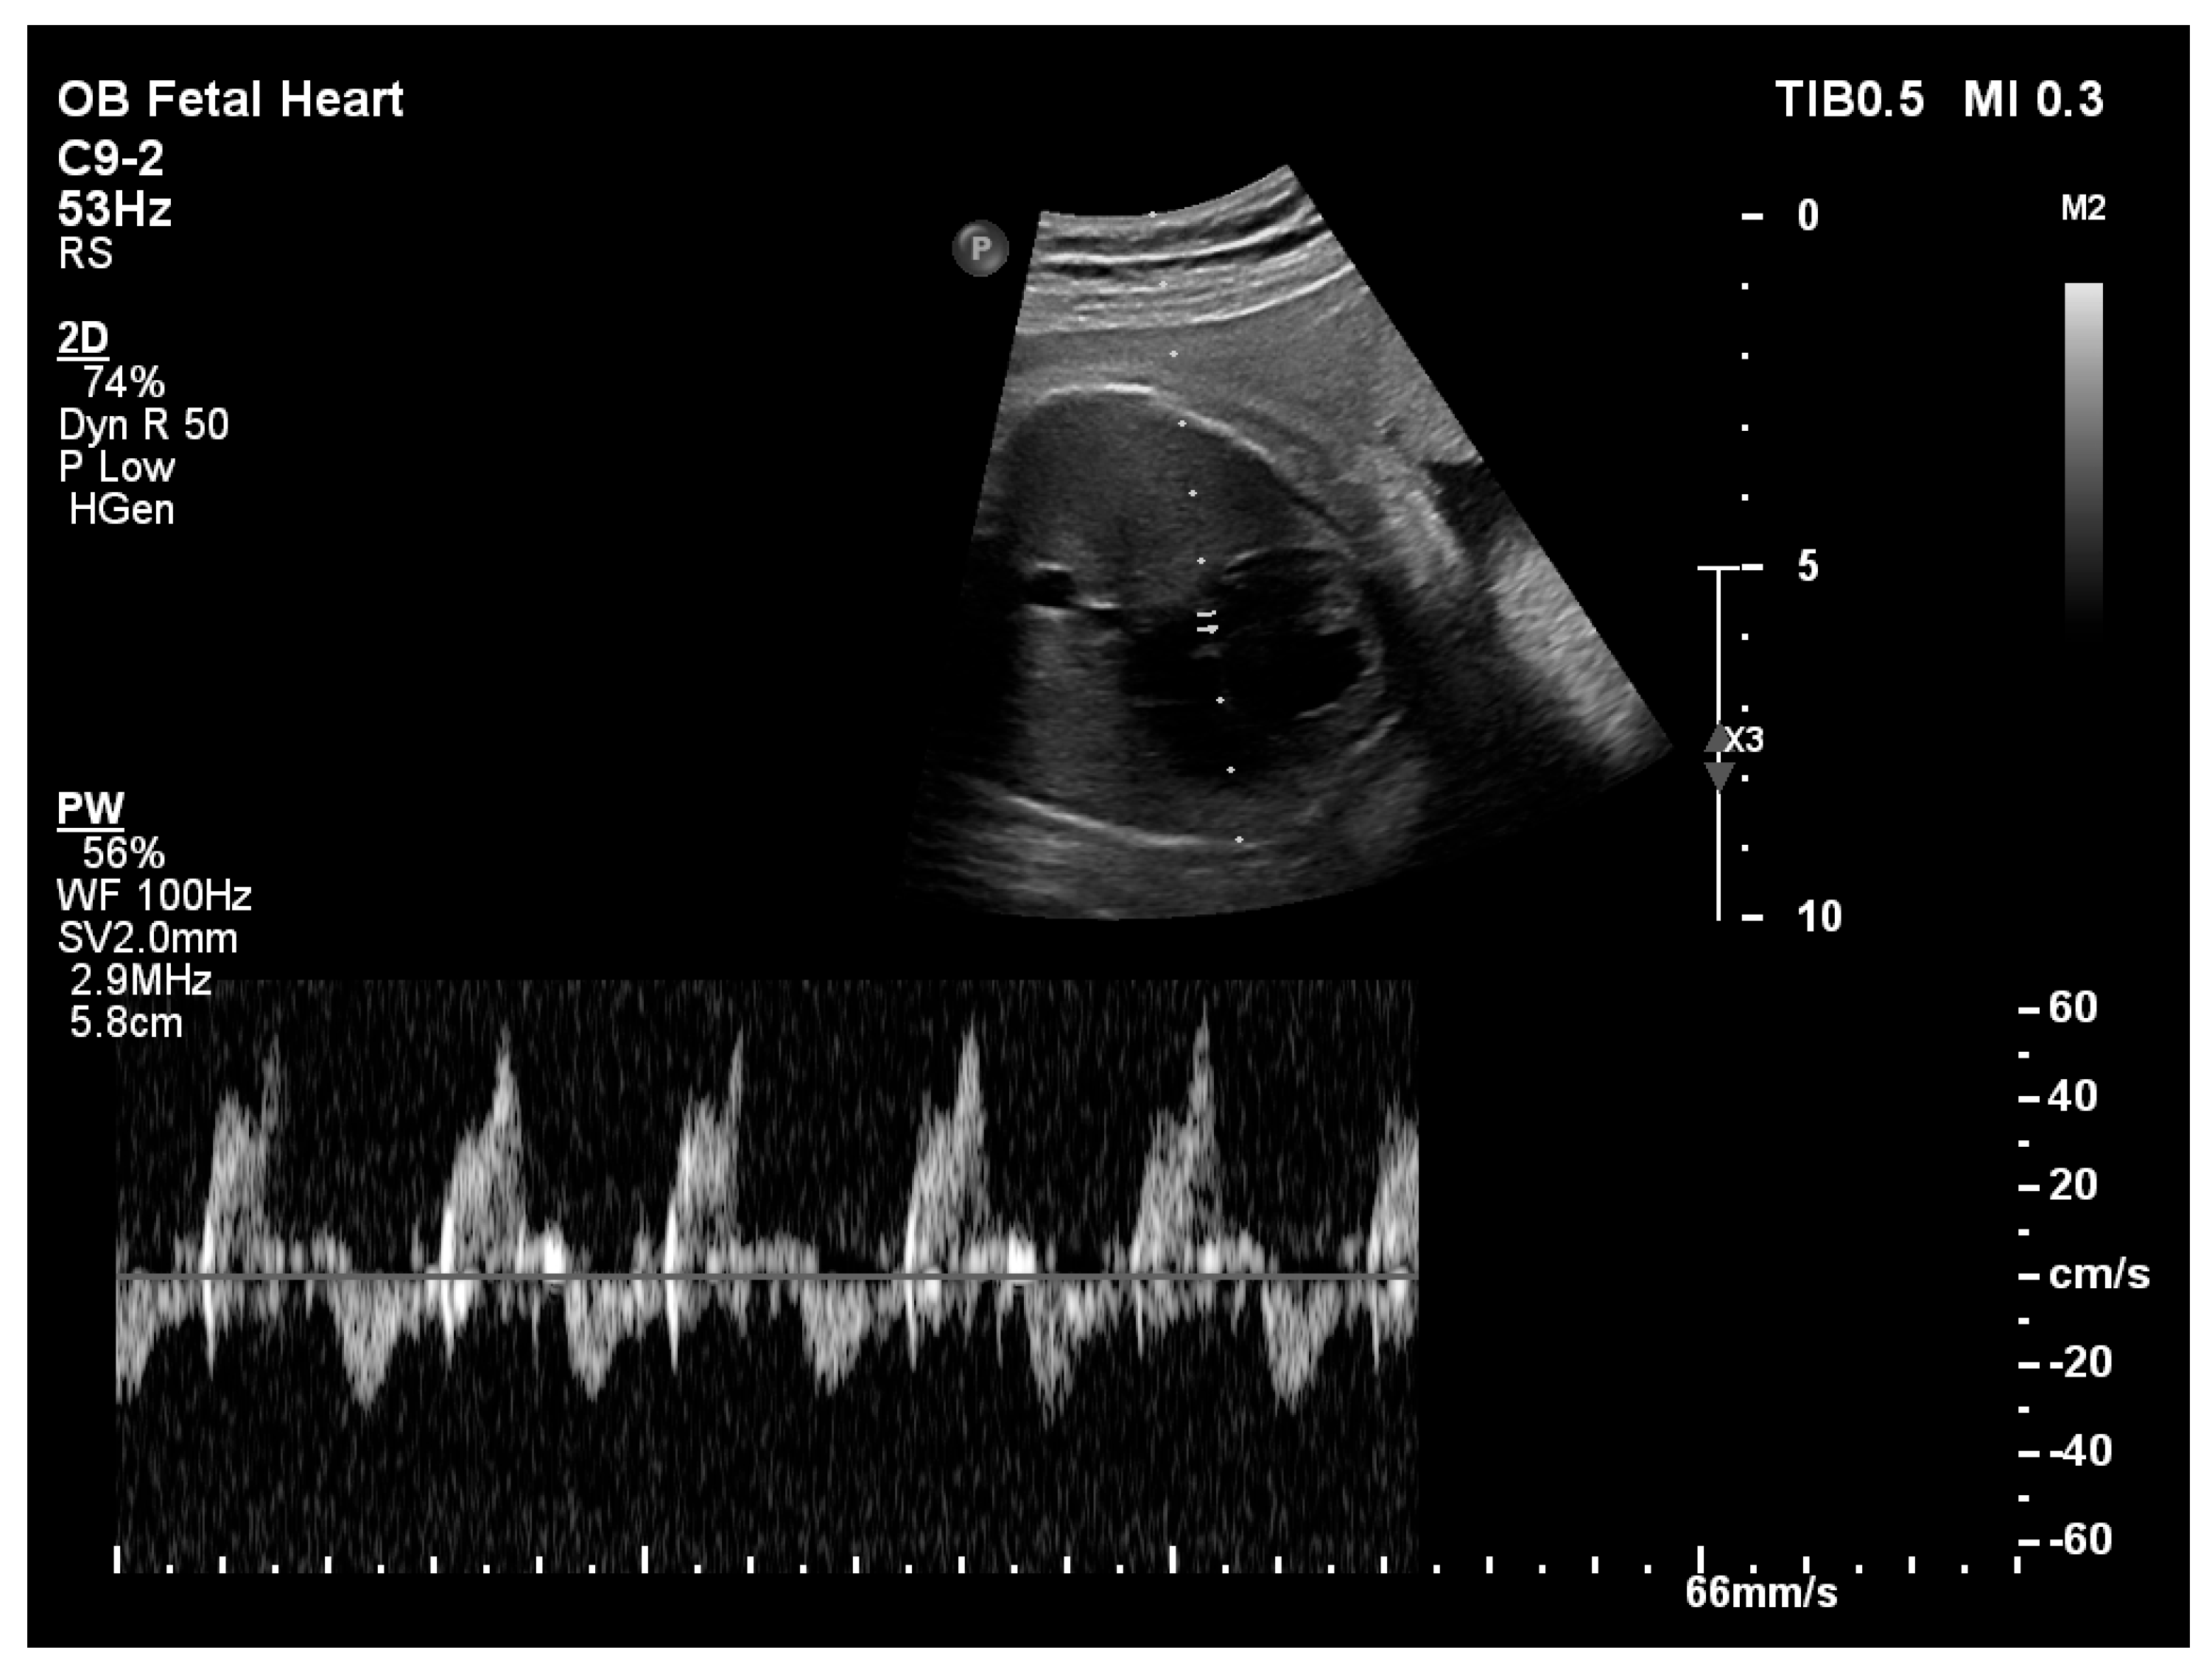

| Biphasic transmitral inflow | Present | Present | Present | Biphasic pattern consistent with impaired LV relaxation |

| LV peak global longitudinal strain (%) | −18.3 | −18.6 | −19.3 | Typical fetal LV pGLS ≈ −16% to −22% |

| Left ventricle peak global longitudinal strain | −18.3% | −18.7% | −21.9% |